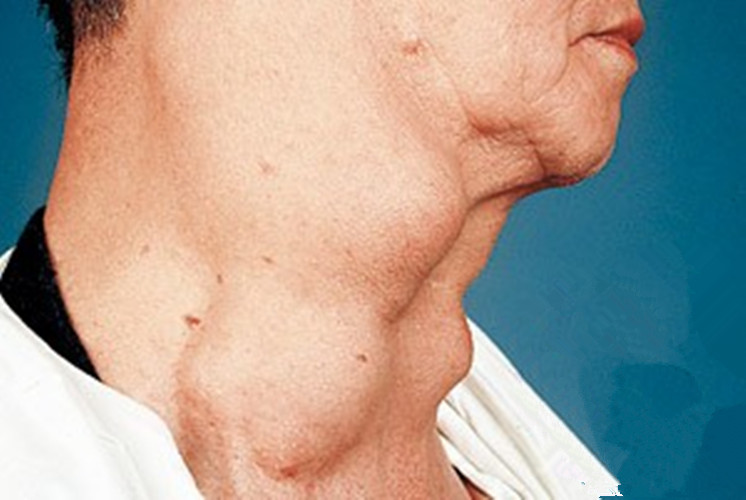

男性出現巨大喉腫瘤的

男性喉腫瘤的症狀

老太太喉腫瘤的